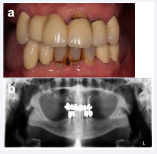

In 2016 the 65 year-old male patients presented himself in our clinic. The general medical history was uneventful. The patient reported that he didn’t care much about his teeth, but with retirement approaching, he wanted to enjoy life again to the full. According to him most of his teeth were extracted due to caries and invasive dentistry. He had received removable dentures some years ago, but didn’t wear them (Figure 11a and Figure 11b).

Figure 11: Initial situation (a) en-face with retracted lips and (b) radiological.

After discussing all the options, it was decided to restore his lower jaw dentition with a root canal treatment for tooth 34 and two cantilever FDPs on either side. The options for the upper jaw were discussed and the patient decided to remove all the remaining teeth and to go for a screw retained FDP on four implants (all-on-4TM).